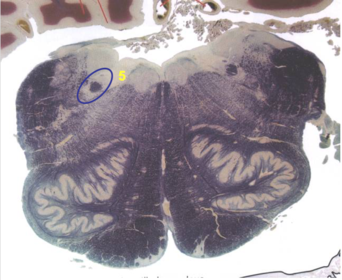

| Longitudinal pontine fibers (corticospinal tract) | |

| Transverse pontine fibers (dark fibers) | |

| Pontine nuclei (pale) | |

| Medial lemniscus | |

| ALS | |

| Trapezoid body | |

| Ventral trigeminothalamic tract | |

| Superior olive | |

| Central tegmental tract | |

| Facial nerve root fibers - descending | |

| Facial motor nucleus | |

| Interposed nuclei | |

| Medial longitudinal fasciculus | |

| Facial nerve root - internal genu | |

| Abducens nucleus | |

| Lateral vestibular nucleus | |

| Superior vestibular nucleus | |

| Inferior cerebellar peduncle | |

| Superior cerebellar peduncle | |

| Dentate nucleus | |

| Fastigial nucleus | |

| Anterior spinocerebellar tract | |

| Spinal nucleus of V | |

| Spinal tract of V | |

| Middle cerebellar peduncle | |